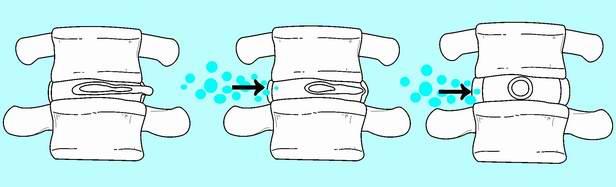

Лечение Межпозвоночной грыжи

Методы лечения грыжи диска

Консервативное лечение грыжи межпозвонкового диска, остеохондроза, артрита, протрузий межпозвонковых дисков - всегда проводится комплексно. Для консервативного лечения грыж межпозвоночных дисков проводятся лекарственная терапия, массаж, тракция позвоночника, ЛФК. Применяется методика НИИ им.Бурденко Н.Н.

-Осуществляется разгрузка позвоночника, путем увеличения расстояния между позвонками;

-уменьшаются мышечные контрактуры;

-снижается внутридисковое давление;

-увеличивается вертикальный диаметр межпозвонкового отверстия, что ведет к декомпрессии корешка и уменьшению отека;

-устраняется подвывих межпозвонковых суставов, что дает декомпрессующий эффект.